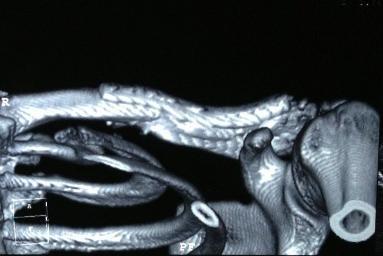

Диагностика болей в ключице

Самое четкое изображение можно получить при КТ плечевого сустава

Чтобы понять, почему возникла болезненность, нужно обратиться к врачу-ортопеду. Он назначит подходящие анализы и диагностику, которая обычно состоит из следующих процедур:

- рентген плечевого сустава и ключицы – показывает состояние костей, помогает выявить травмы, остеомиелит и артриты;

- КТ и МРТ – тонный и информативный способ диагностики, показывающий состояние не только костей, но и структур рядом с ними;

- артроскопия – устаревший эндоскопический метод, который используется очень редко, но дает точные результаты путем исследования внутренней части сустава;

- УЗИ – доступная процедура, которая показывает состояние суставной сумки.

Диагностика и лечение

При первом обращении делают рентген, чтобы проверить целостность костей

При подозрении на любое заболевание пациенту необходимо как можно скорее обратиться за медицинской помощью, чтобы пройти обследование и получить необходимое лечение. Это особенно важно, если речь идет о возможной травме ключичной или плечевой кости.

Основной способ диагностики травм костно-мышечного аппарата – рентгеноскопия. Рентгеновские снимки позволяют врачу с абсолютной точностью определить место и характер смещения, вывиха или перелома ключичной кости, а также убедиться в правильности проведенной коррекции и в динамике наблюдать процесс восстановления поврежденных тканей. В последние десятилетия с этой целью используются также методики ультразвукового исследования, магнитно-резонансной и компьютерной томографии (УЗИ, МРТ, КТ). Они позволяют ставить диагнозы не только при травматических повреждениях, но и при других видах патологических нарушений, являющихся следствием внутренней дисфункции различных систем организма.